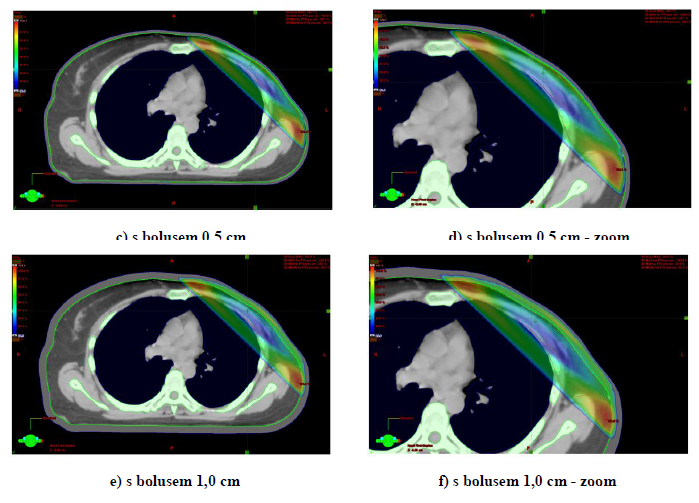

3) Distribuce dávky v oblasti hrudní stěny s bolusem a bez bolusu (TPS Eclipse).

K plánování ozáření s CT skeny používáme simulaci bolusu na hrudní stěně. Tloušťka bolusu ovlivní dávku na povrchu hrudní stěny.

Obr. 1: Distribuce izodoz na hrudní stěně po ablaci pro karcinom prsu